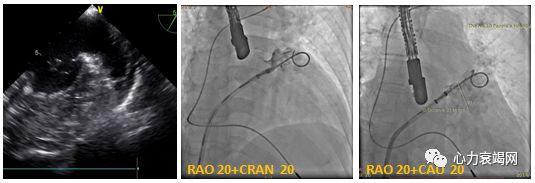

房间隔穿刺:TEE指引下, 用8 FrSL1 穿刺套件, 房间隔后下方

左心耳造影 (RAO20-30+CRAN20/CAU20),测量最大开口直径

TTE:LA内径 54mm,LVEF 61%,微量心包积液

TEE:LA后前径55mm, LAA2叶, 开口内径19 mm, 深度24mm

诊断: 房颤, 永久型,

CHADS2:4分,CHA2-DS2-VASC:6分